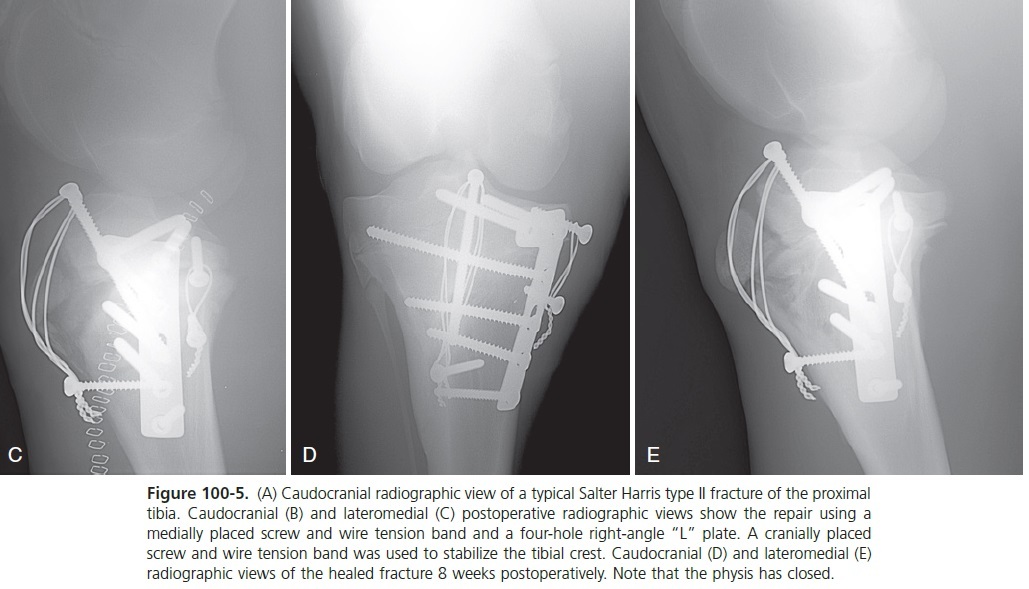

(A) Caudocranial radiographic view of a typical Salter Harris type II fracture of the proximal tibia.

A fter the debris is removed from the fracture, the soft tissue must be elevated along the medial aspect of the proximal tibial physis. If this soft tissue is not elevated, it becomes trapped between the metaphyseal fragment and the physis, preventing complete reduction. Manual downward pressure on the medial aspect of the proximal tibial metaphysis places the intact soft tissue on the lateral aspect of the limb under tension and reduces the fracture. Reduction can be maintained by the placement of one 4.5-mm cortex screw in the epiphysis and one in the metaphysis. A figure-of-eight tension band wire is tightened between the two screws, maintaining reduction during placement of the primary implants if the stability is tenuous (see Figure 100-5, B and C).

The two transverse holes are positioned over the epiphysis closer to the caudal aspect of the proximal tibia, halfway between the femorotibial joint surface and the physis. A right-angle “L” plate with the proximal (short) limb of the plate facing craniad and the long limb of the plate distal along the tibia gives the most diaphyseal contact without the plate overhanging the metaphyseal cortex (see Figure 100-5, B and C). The two proximal screws are inserted across the width of the epiphysis. The screws should be oriented as much as possible parallel to the caudal cortex in a transverse plane, not perpendicular to the plate. The use of 5.5-mm cortex screws is ideal in the epiphysis. The distal screws in the plate are inserted into the metaphysis after using the tension device or are placed in the load position to achieve axial compression.

The new veterinary 4.5/5.0-mm LC P T-plate is ideal for this application (see Figures 77-40 and 100-6, A to D). If an LC P is used, the fracture is reduced, and the locking head screws are placed in the epiphysis first, followed by axial compression of the fracture using a 5.5-mm cortex screw in the load position and finally implantation of the remaining locking head screws in the metaphysis. The presence of a hole for temporary 2-mm pin insertion through the plate into the epiphysis is useful to guide the proper location of the locking head screws since their angle to the plate is fixed and cannot be manipulated. It is desirable to pass at least one of the plate screws across the proximal metaphysis into the lateral metaphyseal fragment that remains attached to the epiphysis or into the lateral epiphysis. This increases the stability of the lateral aspect of the fracture (see Figures 100-5, B and C, 100-6, D and E). The proximal tibial physis can be bridged with this screw and when the screw is removed the physis will normally resume growing.

Tension-band wire The tibial crest remains attached to the epiphysis and is under continual cyclic tension from the patellar tendon attachments. Neutralization of this force greatly aids stability. The most stable fixation is achieved with a tension-band wire used to stabilize the tibial crest. A 5.5-mm cortex screw is placed from proximal to distal through the epiphysis and into the metaphysis to act as the proximal anchor for the tension-band wire. A distal screw in the metaphysis or a hole through the cranial aspect of the metaphysis is used for the distal anchor of the tension band. One or two strands of 1.5-mm wire are placed in “figure-of-eight” fashion and twisted to tighten the construct (see Figures 100-5, B and C, and 100-6, C and D). Alternatively, a 1-mm cable can be substituted for the wire. The proximal screw is left above the bone surface under the patellar ligaments and not tightened down to the surface of the bone to allow removal at a later date.

If the 4-week follow-up radiographs indicate healing, exercise is increased over the next month to unrestricted exercise by 8 weeks. If no complications are encountered and the physis has not closed, the implants can then be removed after 8 weeks to allow the physis to resume growth if growth potential remains (see Figures 100-5, D and E, and 100-6, E).